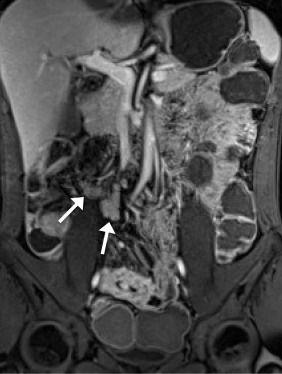

Enlarged mesenteric lymph nodes were most clearly seen on the postcontrast VIBE images, presenting as ovoid or lobulated nodular lesions between the mesenteric vessels (Figure 1 ). Engorged vasa recta were often identified adjacent to an active inflamed intestinal loop and were also best demonstrated on the postcontrast VIBE images (Figure 2 ). Fibrofatty proliferation was best seen on the coronal T2-weighted half-Fourier single-shot turbo spin-echo (T2-HASTE) images that presented as increased mesenteric fat surrounding the affected intestinal loops (Figure 3 ). Fistula tracts were often identified between an inflamed bowel and adjacent structures, showing tethering of the two structures with a contrast-enhanced fistula tract between them (Figure 4 ). Meanwhile, abscesses often manifested as fluid collections with a high signal on T2-HASTE images and well-enhanced walls on the postcontrast VIBE images (Figure 5 ).

A 36-year-old man. Coronal postcontrast VIBE image shows several enhancing ...

Figure 1.

A 36-year-old man. Coronal postcontrast VIBE image shows several enhancing enlarged lymph nodes on the mesentery (arrows). VIBE = volumetric interpolated breath-hold examination.